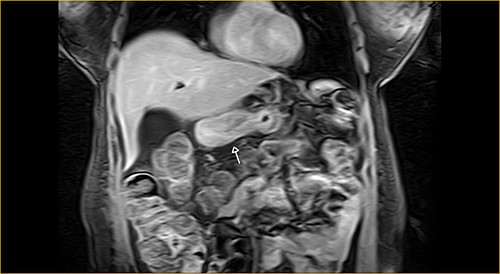

Laboratory examination showed anemia. An excluded stomach distention and parietal thickening of the pylorus and antrum were identified during abdominal computed tomography (CT) and magnetic resonance imaging (Figs 1–4). Thoracic CT was normal.

Coronal section on contrast magnetic resonance showing excluded stomach distention with parietal thickening of the pylorus and antrum (arrow).